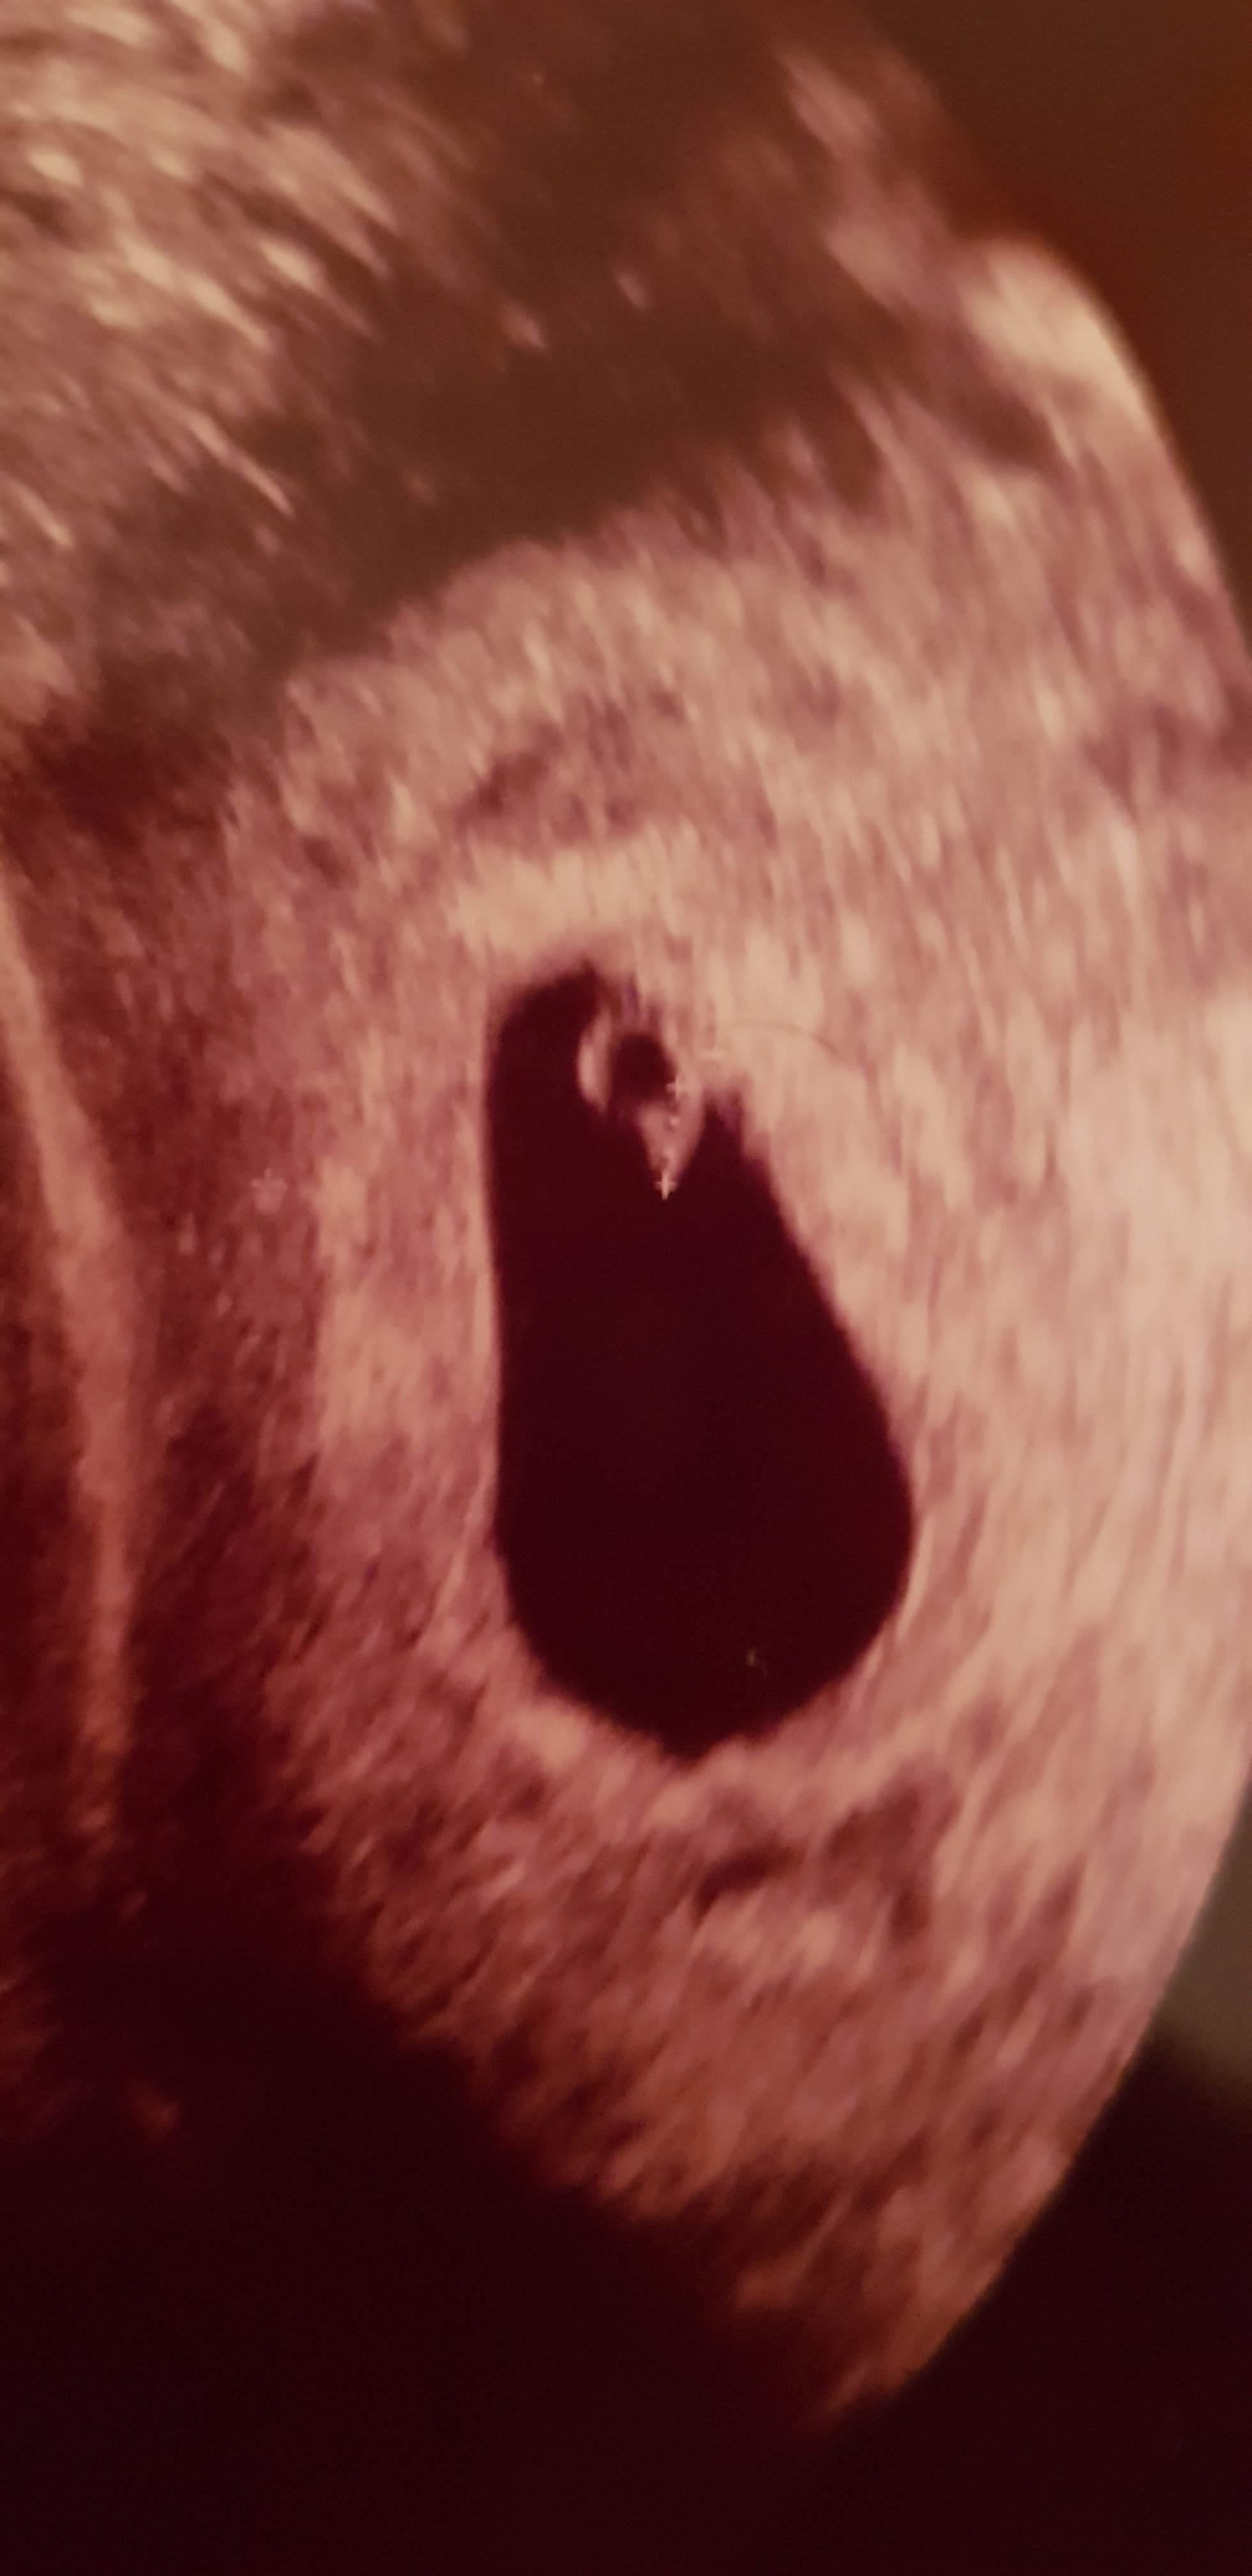

Witam się w 6+0:)

Wczoraj pierwsze USG, dzidzia ma 0.27cm i mamy pikajace serduszko :)

Termin porodu na 12.12